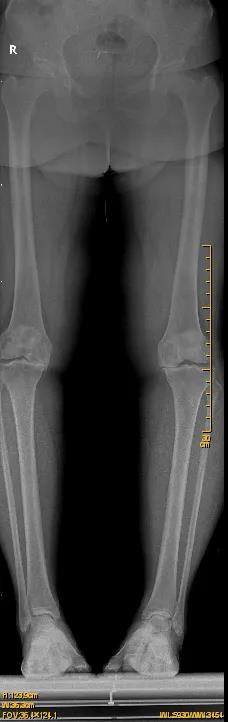

来自东石镇的患者施女士今年52岁,近年来由于双膝关节的严重退变,行走十分困难,生活质量受到了严重的影响。施女士曾辗转多家医院就诊,医生均明确告知需手术治疗才能彻底解决问题,但如果双侧膝关节同时手术治疗,费用动辄十几万,施女士不由压力倍增。

因施女士有冠心病支架植入病史,术前通过心内科、麻醉科多学科会诊后,决定一期行右全膝关节置换术,二期再行左侧膝关节置换手术治疗。8月4日,在张金山副院长的带领下,为施女士顺利地进行了右侧人工全膝关节置换术,手术效果十分显著。